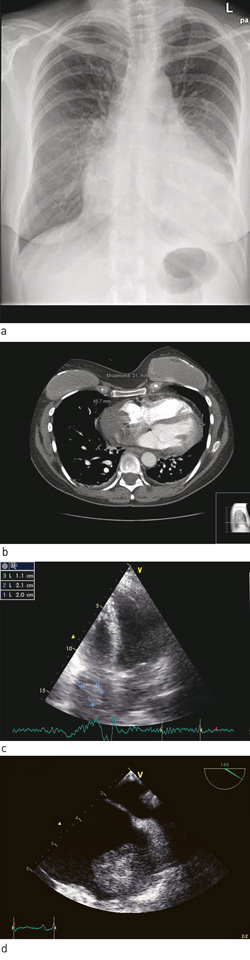

Det var startet med tumornekrosefaktor-α-hemmer i tillegg til behandling med metotreksat, selv om den revmatologiske sykdomsaktiviteten ble vurdert å være lav. Den siste uken før innleggelsen hadde hun knapt orket å gå ut av leiligheten sin. Det ble før innleggelsen startet med behandling med fenoksymetylpenicillin på grunn av mistenkt luftveisinfeksjon, uten at dette hadde effekt på symptomene. Røntgen thorax tatt før innleggelsen viste betydelig økt hjertestørrelse, og blodtrykket var kun 84/60 mm Hg. Innleggelsesdiagnosen var derfor hjertesvikt.

Røntgen thorax ga mistanke om perikardvæske (fig 1a). Dette ble verifisert ved ekkokardiografi, som viste væske i perikard rundt store deler av hjertet, med største bredde på 2,5 cm bak venstre ventrikkel. Venstre ventrikkel hadde gode kontraksjoner i alle avsnitt, noe som sammen med normale troponin T-verdier talte imot myokarditt. Imidlertid var høyre ventrikkels funksjon litt redusert, og det ble bemerket at høyre sides laterale vegg var fortykket. Pasienten ble dagen etter innleggelsen overført til regionsykehus på grunn av mistanke om truende hjertetamponade og ble tappet for 1 200 ml blodtilblandet perikardvæske.

Pasienten ble denne gang utredet med CT thorax, som viste en oppfylling i høyre forkammer (fig 1b). Denne ble gjenfunnet ved transtorakal ekkokardiografi (fig 1c). Videre utredning med transøsofageal ekkokardiografi viste en bredbaset oppfylling i høyre forkammer på 5,1 cm × 5,7 cm (fig 1d). Pasienten ble overført til regionsykehus for nærmere diagnostisering av oppfyllingen.